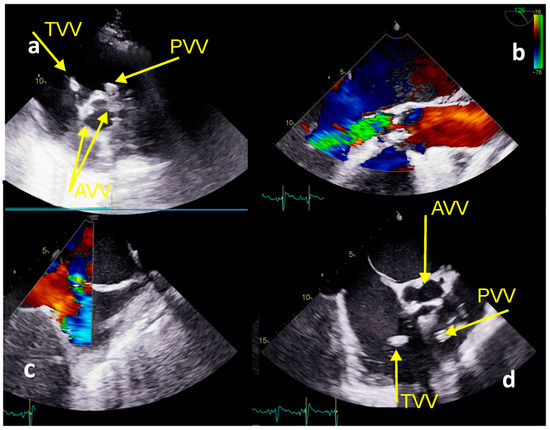

2.1. Case Report No 1